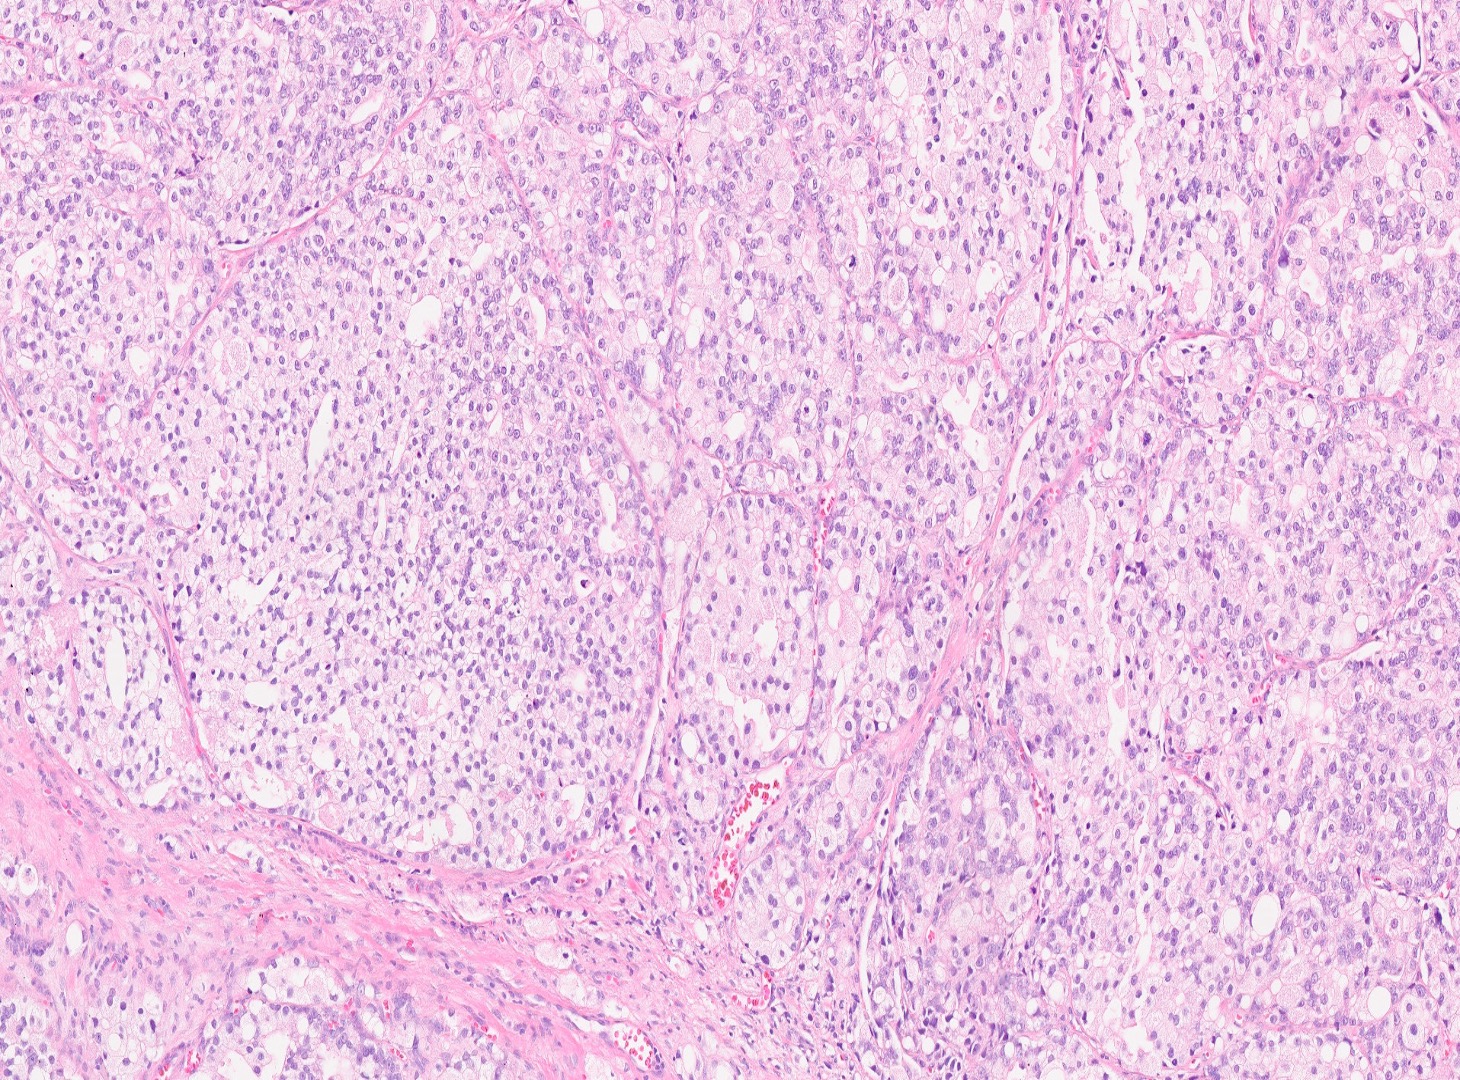

The patient is a 72-year-old male with a history of urinary hesitancy and nocturia, previously attributed to benign prostatic hyperplasia (BPH). He presented to his primary care physician with a 3-month history of unintentional weight loss (~12 lbs), fatigue, and right upper quadrant abdominal discomfort. No history of jaundice, hepatomegaly on exam, or alcohol use disorder. A CT abdomen/pelvis with contrast revealed multiple hypodense lesions in both hepatic lobes, the largest measuring 3.1 cm in segment VI, concerning for metastatic disease. The prostate was enlarged, but no discrete mass was identified on imaging. Bone scan showed sclerotic lesions in the pelvis and lumbar spine, consistent with osseous metastases. A liver biopsy was obtained from the largest lesion in the right hepatic lobe for diagnostic confirmation.

What is the diagnosis?

GU Pathology